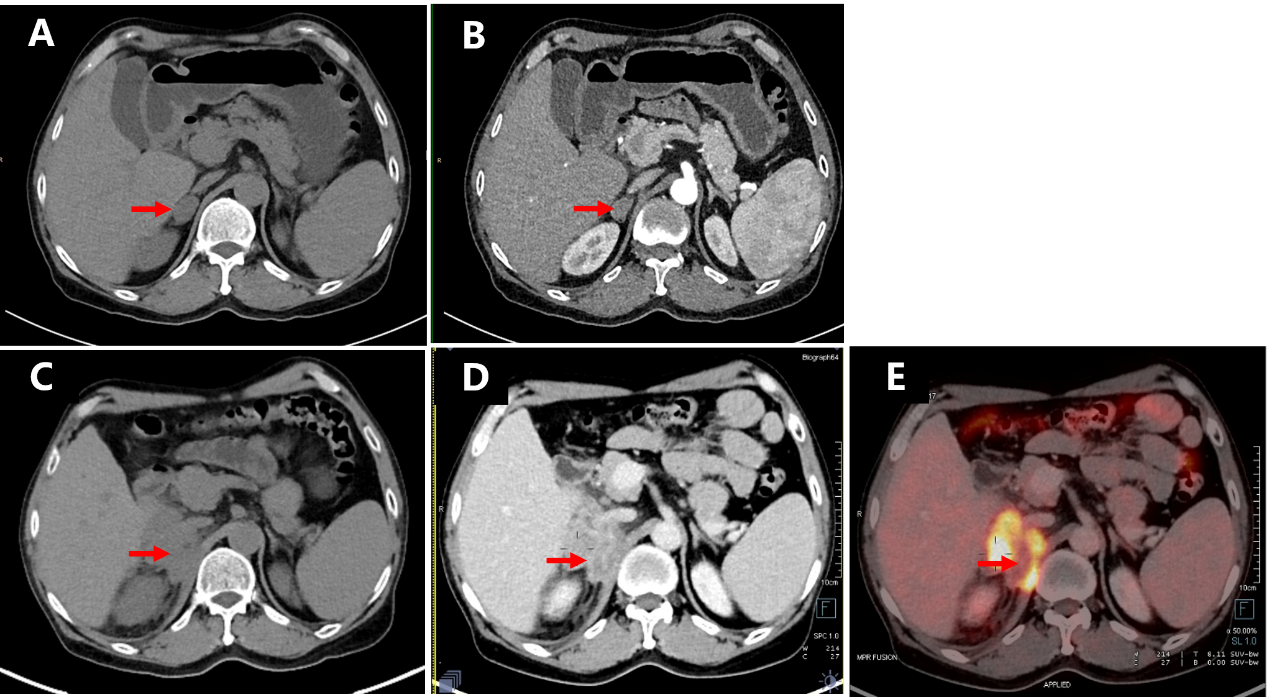

BDUMP is often considered a precursor to metastatic malignancy[10]. Given the patient's critically elevated blood pressure (204/118 mmHg), we recommended an immediate referral to the cardiology department for blood pressure management and a comprehensive systemic examination. Abdominal computed tomography (CT) identified a well-circumscribed, homogeneous, and isodense nodule (2.6×1.6×3.4 cm) in the right adrenal limb of the patient (Figure 3A, 3B). The patient was then referred to the urology department for further evaluation. After excluding other abnormalities in the renin-angiotensin-aldosterone system and normal potassium levels, a diagnosis of a nonfunctional right adrenal adenoma was made.

Three months later, during follow-up at an outside facility, CT images showed that the adrenal mass had rapidly enlarged to 56 x 46 x 55 mm, become irregular and inhomogeneous with an unclear boundary with the lower margin of the liver (Figure 3C, 3D). 18F-fluorodeoxyglucose positron emission tomography-CT (PET-CT) demonstrated increased metabolic activity in the right adrenal gland, raising suspicion of a malignant tumor (Figure 3E). An adrenal biopsy was performed, and histopathological examination (Figure 2D) along with immunohistochemical analysis of the adrenal and liver tissue confirmed the diagnosis of ACC with liver metastasis (Figure 3A, 3C). Despite normal tumor markers (including carcinoembryonic antigen, alpha-fetoprotein, CA125, CA15-3, and CA19-9), the patient was diagnosed with ACC with liver metastasis. Unfortunately, by the time of definitive diagnosis, the patient was no longer a candidate for surgery due to extensive hepatic involvement. He succumbed to disease progression five months post-diagnosis, with an overall survival of 12 months from the onset of ocular symptoms.

Figure 3 Initial and follow-up diagnostic CT images and follow-up PET-CT image of the right adrenal gland of this patient

Figure 3. Initial and follow-up diagnostic CT images and follow-up PET-CT image of the right adrenal gland of this patient

A) On initial diagnostic plain scan CT image, a 26 x 16 x 34 mm uniform and isodense nodule with smooth margin was observed in the inner limb of the right adrenal gland. B) The nodule showed moderate and homogeneous enhancement on the enhanced scanning. C) On follow-up diagnostic plain scan CT image, an approximately 56 x 46 x 55 mm irregular and inhomogeneous mass shadow was seen in the right adrenal gland, and the boundary with the lower margin of the liver was unclear. D) The mass had obvious inhomogeneous enhancement on the enhanced scan. E, An irregular mass in the right adrenal area of the retroperitoneum showed increased glucose metabolism on the follow-up PET-CT image.